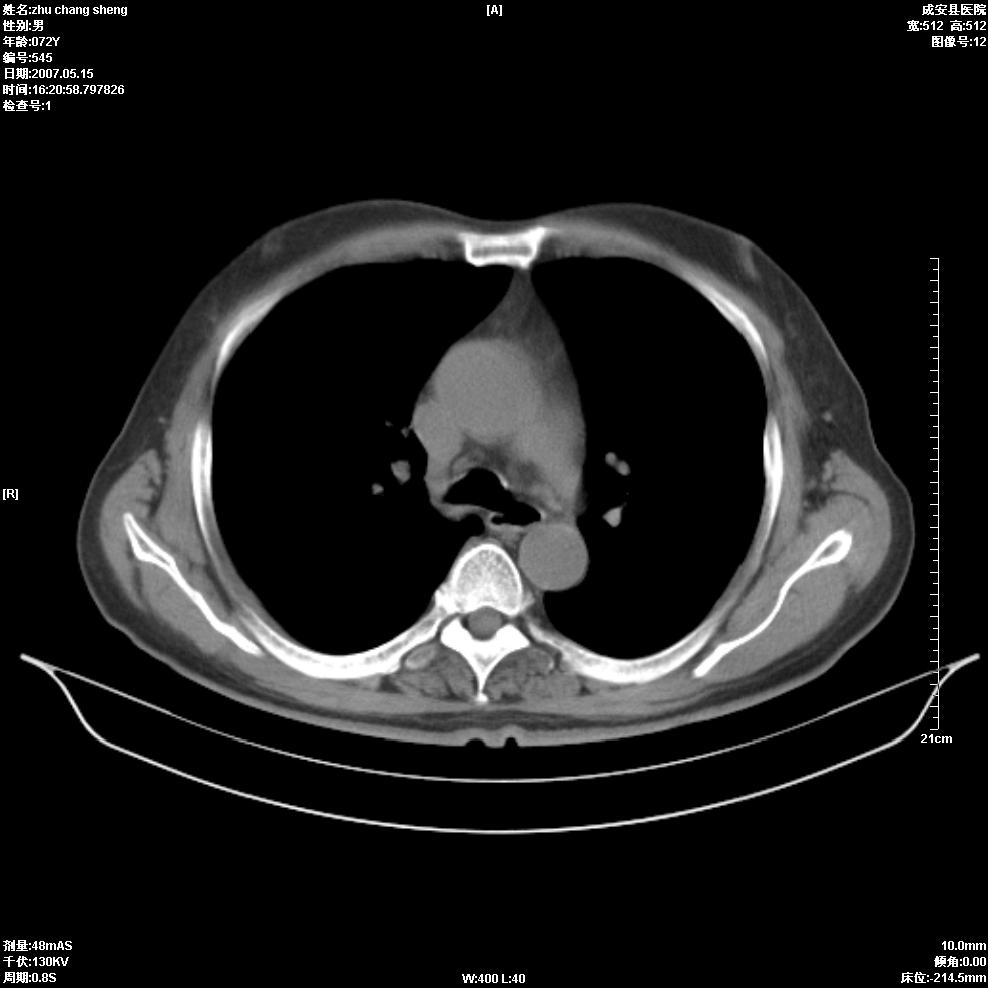

以下是引用医博云天在2007-5-15 19:10:00的发言:[br]心包积液,胸腔积液,心影增大,左心为主。

以下是引用zhangzhongshou在2007-5-15 20:21:00的发言:[br]心包积液可以肯定有,肿块显示不清,建议增强或mri检查。

以下是引用jinning在2007-5-15 21:06:00的发言:[br]心包积液可以肯定,建议增强或mri检查吧!

以下是引用拾荒者在2007-5-15 22:28:00的发言:[br]心包膜增厚,有少量积液,右室前壁示均匀软组织密度影,边界欠清,建议增强扫描或mri检查与室壁瘤鉴别。

以下是引用还珠格格在2007-5-19 9:50:00的发言:[br]病人与5月18日 做了核磁增强扫描 确诊为前上纵隔侵袭性胸腺瘤。